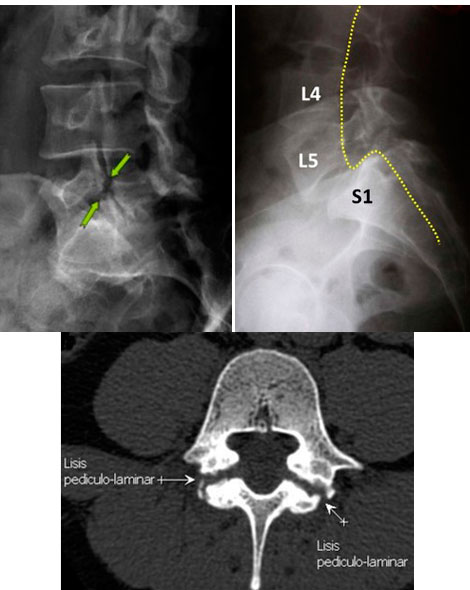

DIAGNOSTICO:

Estudios Radiográficos: